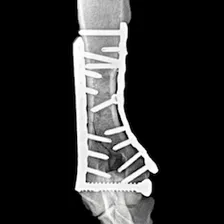

Cutting-edge surgical techniques supported by the latest evidence; TPLO for cruciate ligament tears. Management of patellar luxation, elbow, shoulder, hip & tarsal joint disease, complex fractures & limb deformities.

Our highly trained, experienced, & knowledgeable surgeon utilises state-of-the-art equipment & implants to provide advanced yet cost-effective surgical treatments. Enjoy peace of mind as you focus on your pet's recovery.